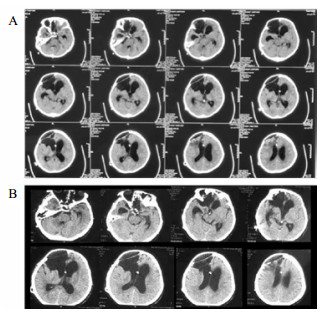

将分流管压力降为0.5后的第6天,该患者复查头颅CT和意识水平均无明显改变;后经分流储液囊穿刺脑脊液外引流,每日引流量150 mL,持续10 d,仍无明显改变。再将脑脊液外引流量增至300 mL/d,患者行为学稍有变化,开始出现刺激后头部转动、手部摸索活动,眼球能视觉追踪。复查头颅CT示脑室形态略缩小。因此,在此基础上再次手术将分流管由原来的抗虹吸可调压管更换为非抗虹吸可调压管,压力设为1.0。患者意识水平进一步改善,术后第4天复查CT示脑室较前缩小(图 2),其大小形态接近正常。随访一年,患者生活能自理,E-GOS 5分。

| 图 2 病例1更换分流管后第4天头颅CT |